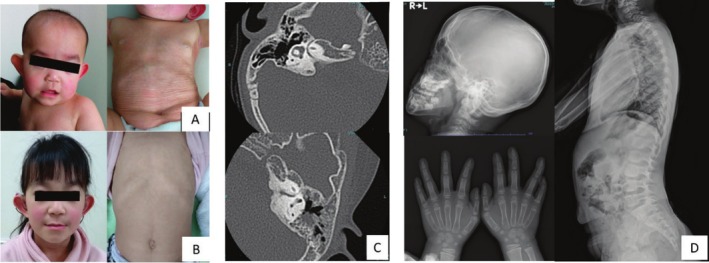

Results: A 5-year-old girl presented with congenital skin wrinkles and was initially diagnosed with congenital cutis laxa. She had bilateral inner ear hypoplasia, bilateral low-frequency hearing loss, attention-deficit/hyperactivity disorder, and mild intellectual disability. Physical examination revealed protruding ears, frontal bossing, and dental malalignment. A de novo heterozygous missense variant in the PTDSS1 gene, c.284G>A (p. Arg95Gln) was identified by WGS. Functional analysis indicated increased PS synthase activity, supporting the pathogenicity of this variant.

Conclusions: The patient's cutis laxa and facial features were consistent with LMS, though radiographic findings did not reveal the characteristic sclerosing bone dysplasia reported in previous cases. This observation suggests that LMS may have a broader phenotypic spectrum than previously recognized.